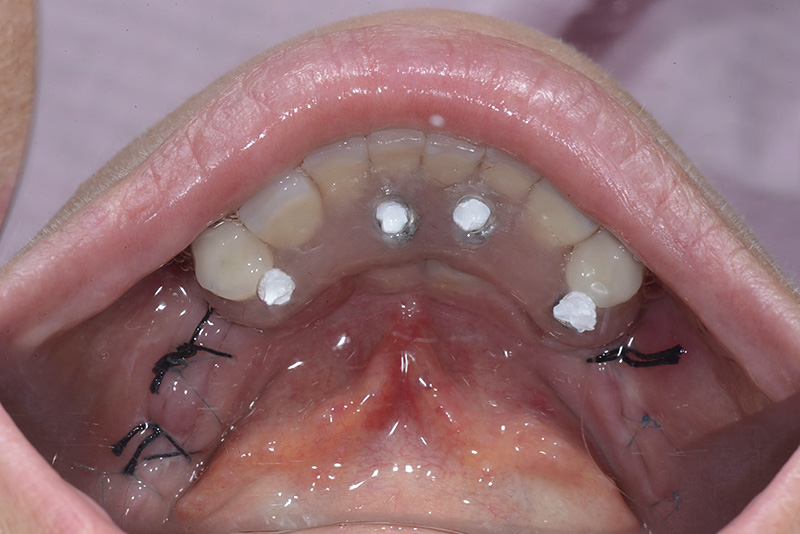

PREMESSA: in seguito all’estrazione dell’incisivo laterale superiore di destra, resasi necessaria per cause batteriche, si decide di affrontare il caso con il posizionamento di un impianto in sostituzione dell’elemento mancante dopo guarigione del sito infetto. Con tecniche rigenerative sia dei tessuti ossei mancanti a causa dell’infezione pregressa, sia dei tessuti gengivali che appaiono inizialmente troppo spostati in alto, si ripristina una corretta morfologia delle parabole (contorni) gengivali e delle papille interdentali (triangoli di gengiva tra due denti vicini).

Vengono utilizzati 2 tipi di provvisori: il primo, cementato ai denti vicini, viene utilizzato dal momento dell’estrazione del dente fino ad impianto osteointegrato (circa 6 mesi); il secondo, avvitato direttamente all’impianto, ha una funzione di prova estetica ma soprattutto di guida per la maturazione dei tessuti gengivali peri-implantari portandoli verso la maturazione completa prima di posizionare la corona finale in disilicato di litio.